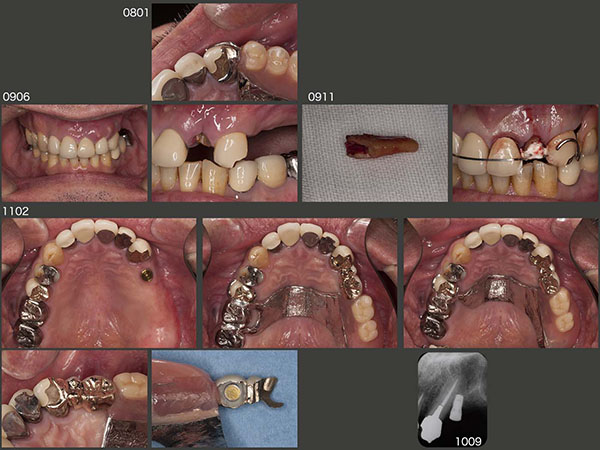

4.犬歯を守るためインプラントを使用

2005年6月初診,48歳男性.う蝕,根尖病巣,不良補綴装置,上顎義歯の製作等総合的な治療を行い,06年10月に終了した.この患者さんは上下に咬み合っている歯数の多い右側で主に咀嚼するはずであるが,前述症例3の患者さんと同じく,義歯が装着してある左側が咬みやすいとおっしゃっていた.(義歯側が咬みやすいと言った患者さんは,私の知る限りでは2名のみ)

2008年1月,左上3のレストが破折した.レストの強度が足りなかった可能性があるが,確かにこの患者さんは左側咬みなのか?と思った.09年6月,今度は左上2に歯根破折が生じた.幸い,破折部が浅かったので,再植することで保存できた.

患者さんは,相変わらず左側が咬みやすいとのことで,私としては左上3が歯根破折を起こすことだけは何とか避けたかった.左上3が有髄歯ならそれ程心配する必要ないが,2回続けて左側にトラブルが生じたこと,左上3が失活歯であることを考慮し,左上4部に7mmの長さのインプラントを1本埋入した.なお,インプラントの上部構造に磁性アタッチメントを使用したので維持は十分であることから,審美性を配慮し左上3の唇側ワイヤークラスプを除去した.また,インプラントの周囲を開放し,清掃性の向上に努めた.さらに,右上5および7に架かっていたクラスプを1本にして,口蓋を覆う大連結装置の面積を少なくした.

2014年11月のリコールの時,右上5の頰側の歯周ポケットが急に10mmの値を示し,この歯の歯根破折を疑った.しかし,自覚症状はまったくなく,治療を望まなかったので,取り敢えずこのまま経過をみることになった.

しかし,何時抜歯になってもいいように,右上5にあったクラスプを右上4および6に作り直させていただいた.16年7月,ついに右上5に痛みが生じたため,抜歯した.なお,この歯に被っていたメタルボンド冠を支台装置と溶接し,人工歯として再利用した.

2017年10月,右下6の咬合時痛で来院.デンタルX線写真から遠心根の歯根破折と診断し,18年1月,ヘミセクションした.しかし,2月になっても,近心根の圧痛等が改善せず,歯周ポケットも10mmみられるようになったため,近心根も抜去した.なお,抜歯時,歯根の破折線を確認した.18年8月,右下4および5を支台歯とするコーヌス義歯を装着した.20年7月,右下5の内冠がコアごと脱離し,再合着した.コアを作り替えずに,内冠を製作したが,ポストの長さが足りなかったと反省している.

結局,この患者さんの習慣性咀嚼側ははっきりしない.左上3およびインプラントは今のところ何も問題が生じていないが,今後,注意深く経過を観察する必要がある.